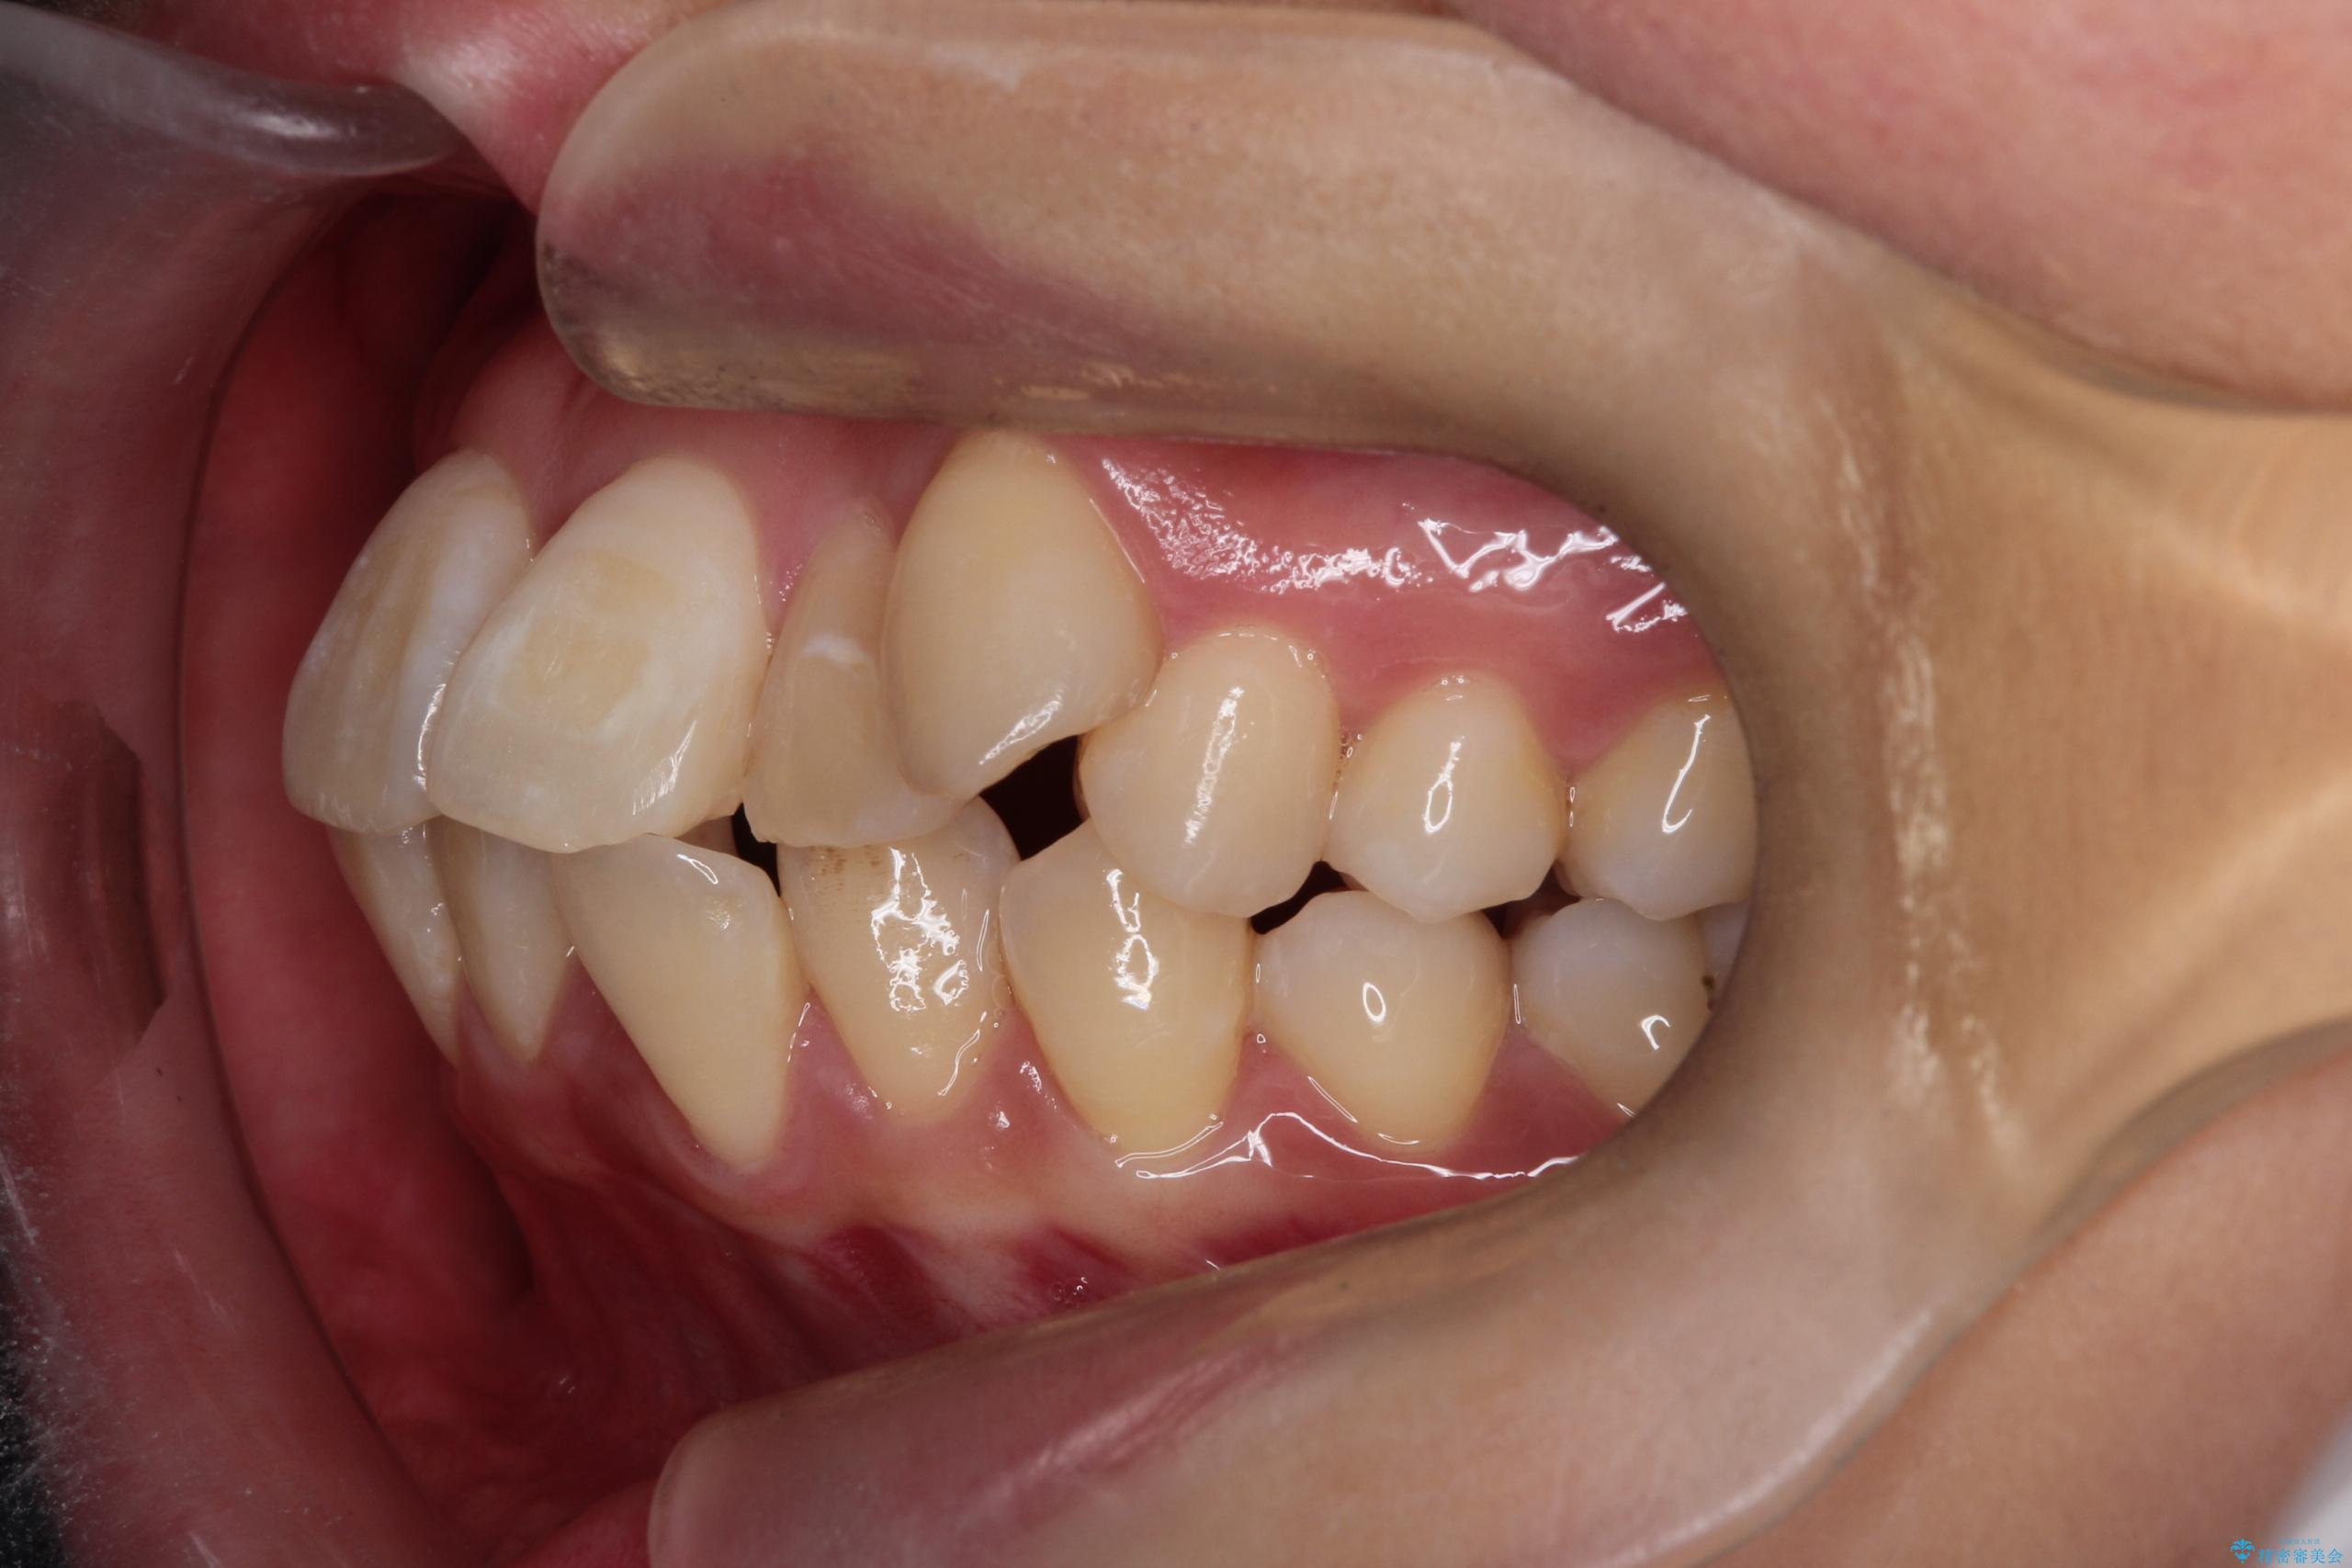

- 八重歯(叢生)と、上下の歯の中心線(正中)がずれていることを主訴にご来院されました。精密な検査の結果、歯列全体のスペースが大幅に不足しており、八重歯を正しい位置に配列し、正中のズレを改善するためには、上下左右の第一小臼歯を抜歯する必要があると診断。装置には、目立ちにくい審美ワイヤーを使用し、見た目を気にせず、機能性と審美性が完璧に整った咬み合わせを目指す治療計画を立案しました。

今回の矯正治療では、まず計画通り上下左右の小臼歯4本を抜歯し、八重歯や正中のズレを解消するための十分なスペースを確保しました。装置には、目立ちにくい白いブラケットとワイヤーを使用した審美ワイヤー矯正を採用。

八重歯: 突出していた八重歯を歯列内に誘導し、デコボコを解消しました。